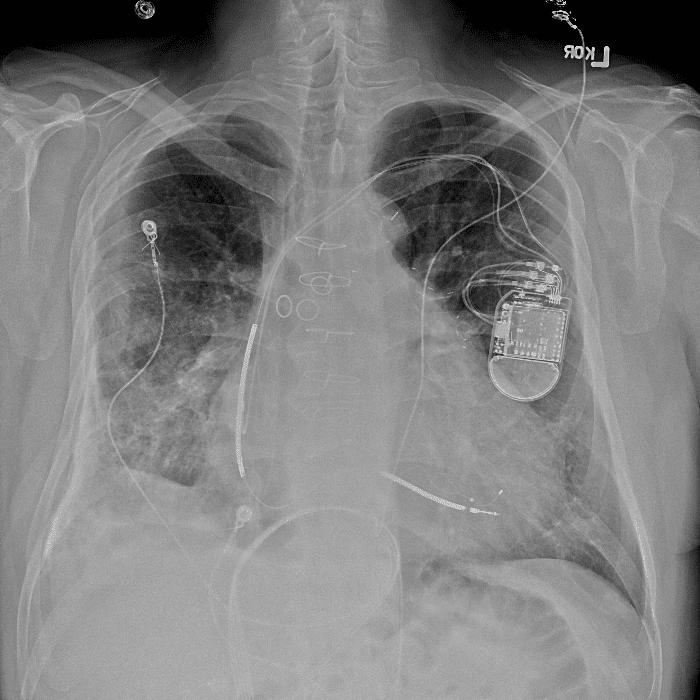

Practice Cases